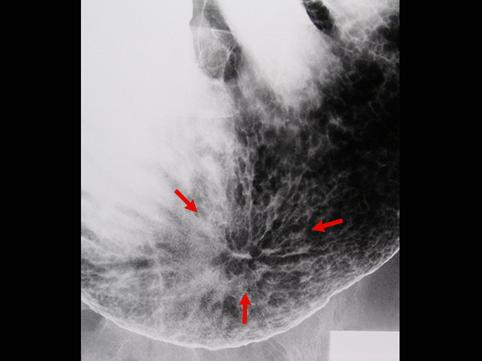

疾病(病理主体)的分类恶性上皮性肿瘤/腺癌

部位(按器官分)胃(部位)/胃角

检查方法X线

肿瘤的肉眼分类0型(表在型)/IIc型(IIc)

肿瘤最大直径30~34

肿瘤的深度m